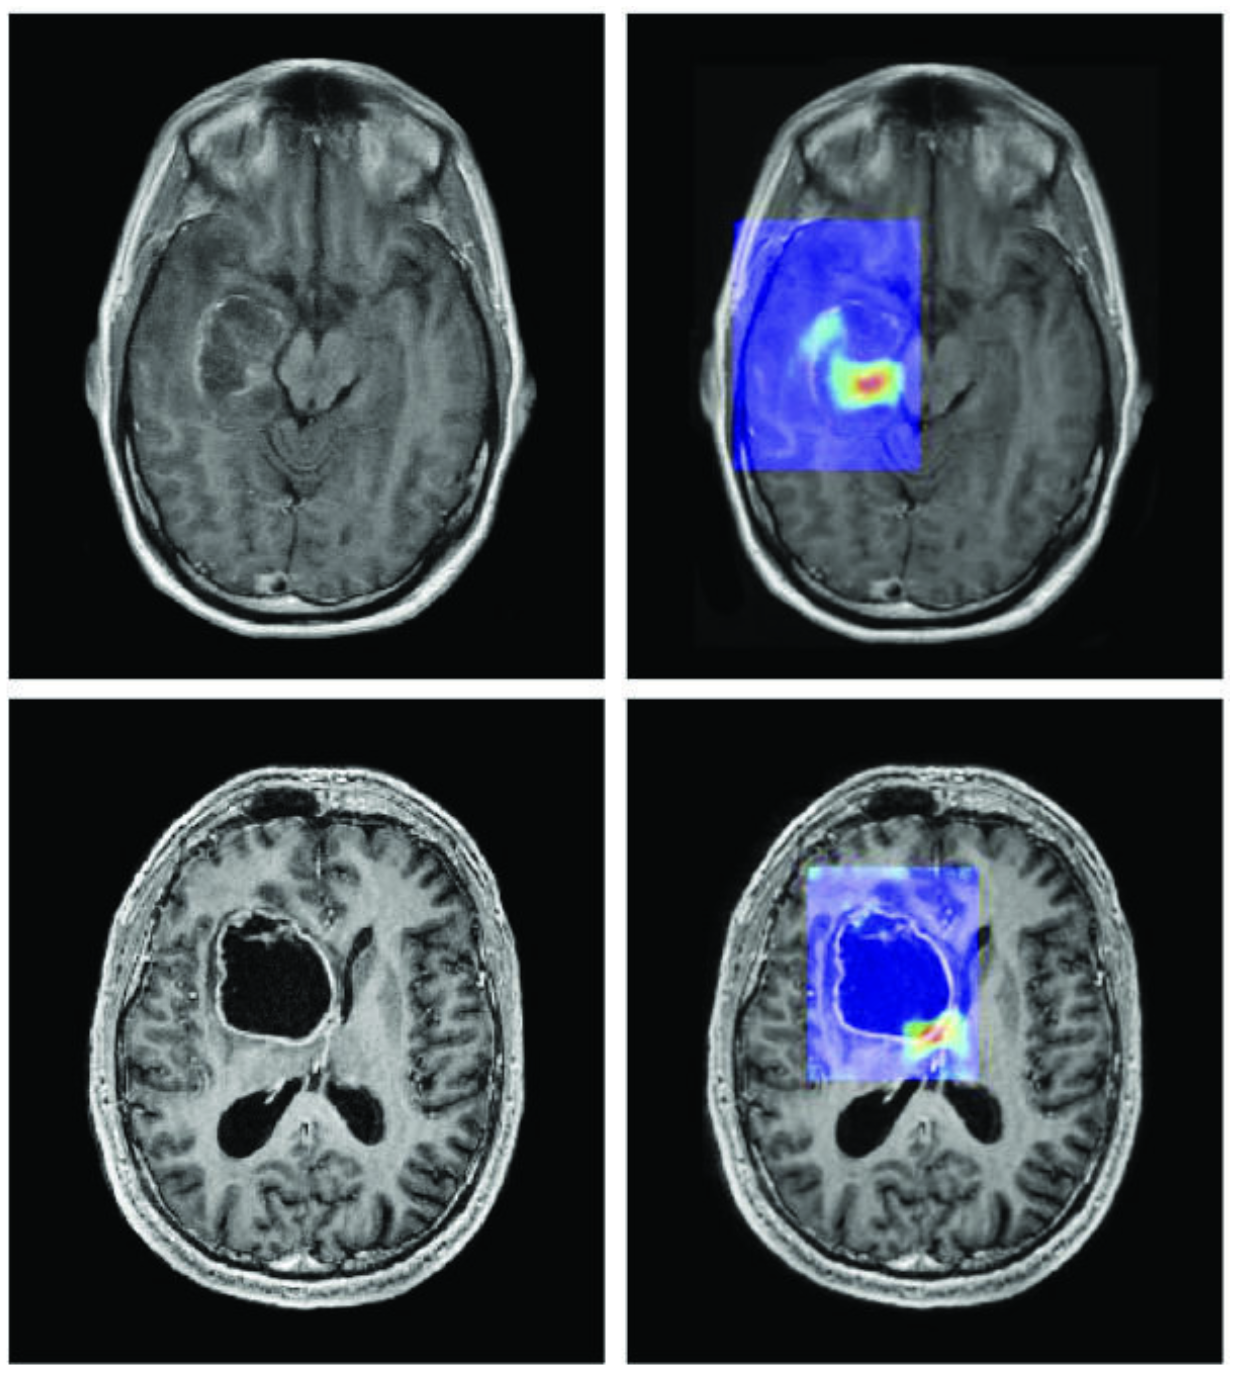

Image extraite de : CA Cancer J Clin mars/avril 2019. DOI : 10.3322/caac.21552. Licence : CC BY 4.0.

Trois situations concrètes illustrent déjà cette coexistence efficace entre l'humain et l'IA. En médecine, des systèmes d'IA analysent des milliers de radiographies en quelques secondes pour détecter des signes précoces de cancer [1], mais c'est le médecin qui interprète le contexte clinique du patient, engage le dialogue avec lui et décide du protocole de soin adapté : l'IA accélère le diagnostic, l'humain en porte la responsabilité et le sens. Dans l'industrie, des constructeurs automobiles utilisent l'IA pour piloter le contrôle qualité sur leurs lignes de production [2], identifiant des défauts invisibles à l'œil nu ; pourtant, ce sont les ingénieurs qui conçoivent les processus, ajustent les seuils de tolérance et prennent les décisions lorsqu'un problème sort du cadre prévu par l'algorithme. Enfin, dans la recherche scientifique, l'IA développée par DeepMind a permis de prédire la structure tridimensionnelle de plus de deux cents millions de protéines [3], un travail qui aurait pris des siècles aux chercheurs seuls ; mais ce sont bien des biologistes et des chimistes qui formulent les hypothèses, conçoivent les expériences et transforment ces prédictions en traitements ou en matériaux nouveaux. Dans chacun de ces cas, la leçon est la même : l'IA ne remplace pas l'humain, elle démultiplie sa capacité d'action.